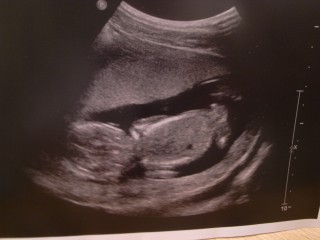

今日ゎ初めての経腹エコーでした。 経腹エコーって事で、午前中仕事休んで旦那サマも一緒に来てくれたのぉ♪♪ いつもゎ動いてくれないんだけど、、、パパもいたからか、おしゃぶりしたり、可愛らしい動きいっぱいしてくれました(´艸`) 順調に成長してて一安心!!!!!! あ~早く性別知りたいなぁぁフフフ

指をおしゃぶり中♪まだ性別はわかりません。胎盤が少しわかるようになってきたと先生が。今の所順調です。

もう赤ちゃんの形をしているのでびっくり!!後ろ姿が何とも言えないかわいさ。

心臓が4つのお部屋に分かれているのが確認出来ました。耳がパパ似?!